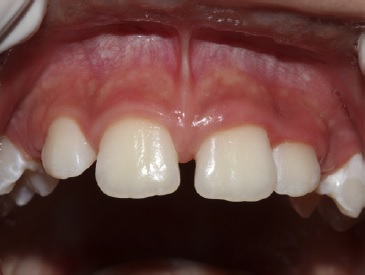

Paciente de oito anos de idade, sexo feminino, procuro a Clínica Integrada do Curso de Odontologia do Centro Universitário Ages (UniAges) juntamente com seu responsável para consulta dentária. Durante a anamnese e o exame clínico, foi observada a presença de freio labial superior fibroso que produzia isquemia ao ser tracionado e espaço interincisal (Figura 1), além de histórico hereditário paterno de diastema. Foi realizada radiografia periapical da região para avaliação dos dentes e das estruturas de suporte. A paciente estava na fase de dentição mista com a presença dos incisivos centrais e laterais superiores permanentes; com ausência dos caninos permanentes, ainda em processo de erupção dentária, não apresentava inflamação gengival, controle satisfatório de biofilme (menor que 20%) nem alteração sistémica. Assim sendo, diante da avaliação foi sugerido a cirurgia de frenectomia do freio labial superior.